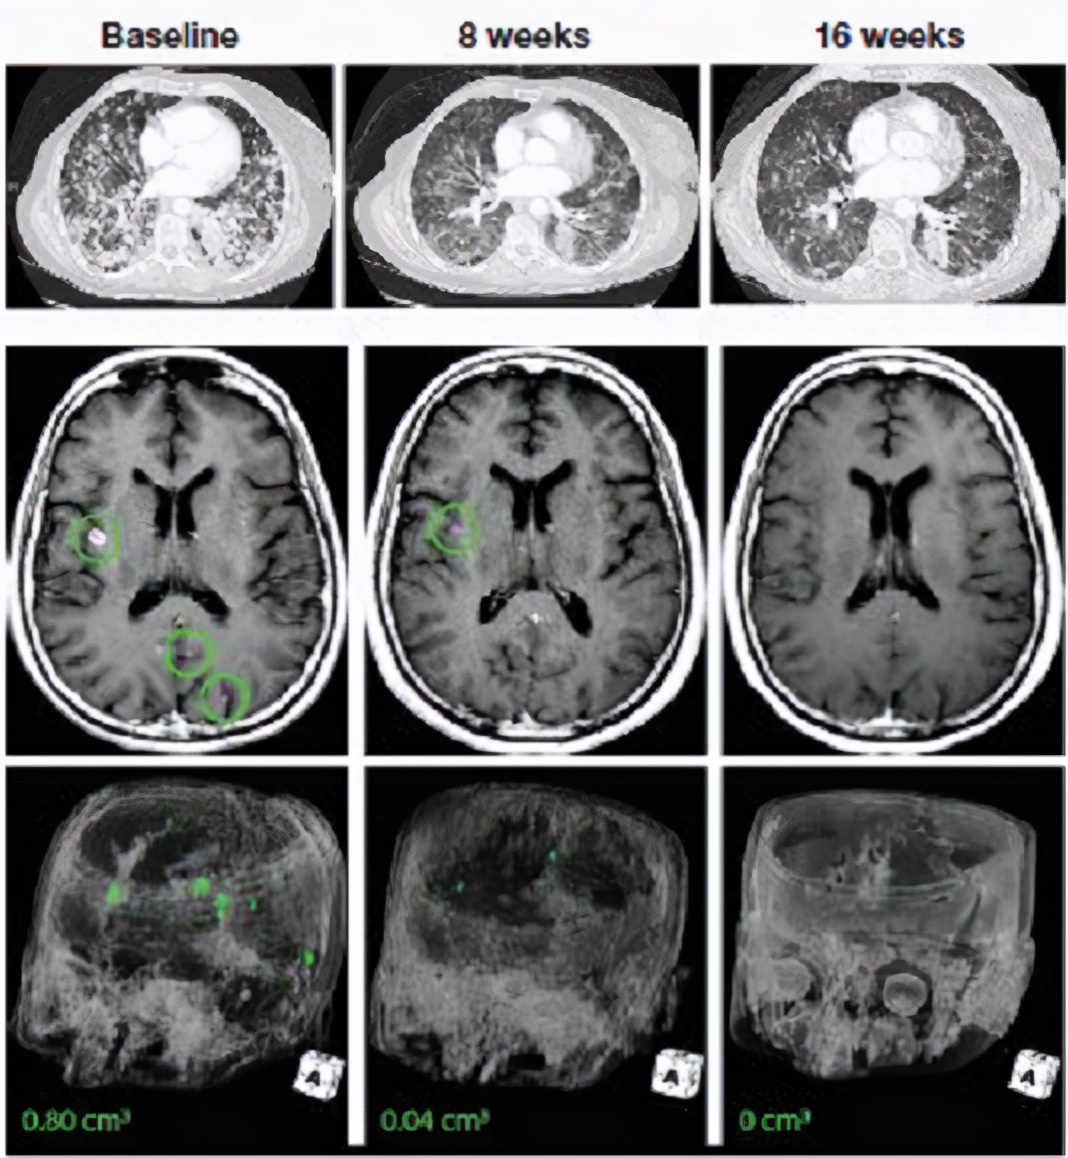

肺癌脑转移:一线治疗,脑部肿瘤几乎全部消失

一位78岁的女性既往没有接受过任何治疗的晚期肺癌患者,确诊时已经出现了严重的脑转移,拒绝接受化疗,基因检测后发现存在EPS15-NTRK融合。

接受拉罗替尼治疗后,肺部的病灶缩小了34%。脑部的转移灶几乎全部消失(减少95%)。